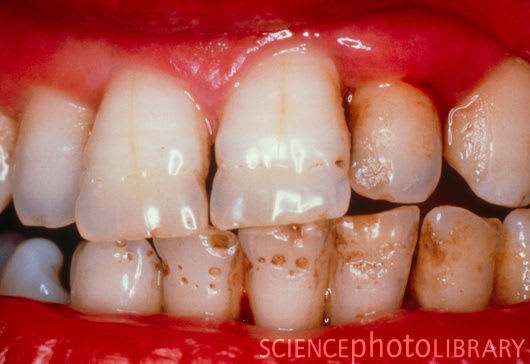

Tiens pour ta collection de photos, avec un clin d'oeil pour les odf...

Email vw4eh2 - Eugenol